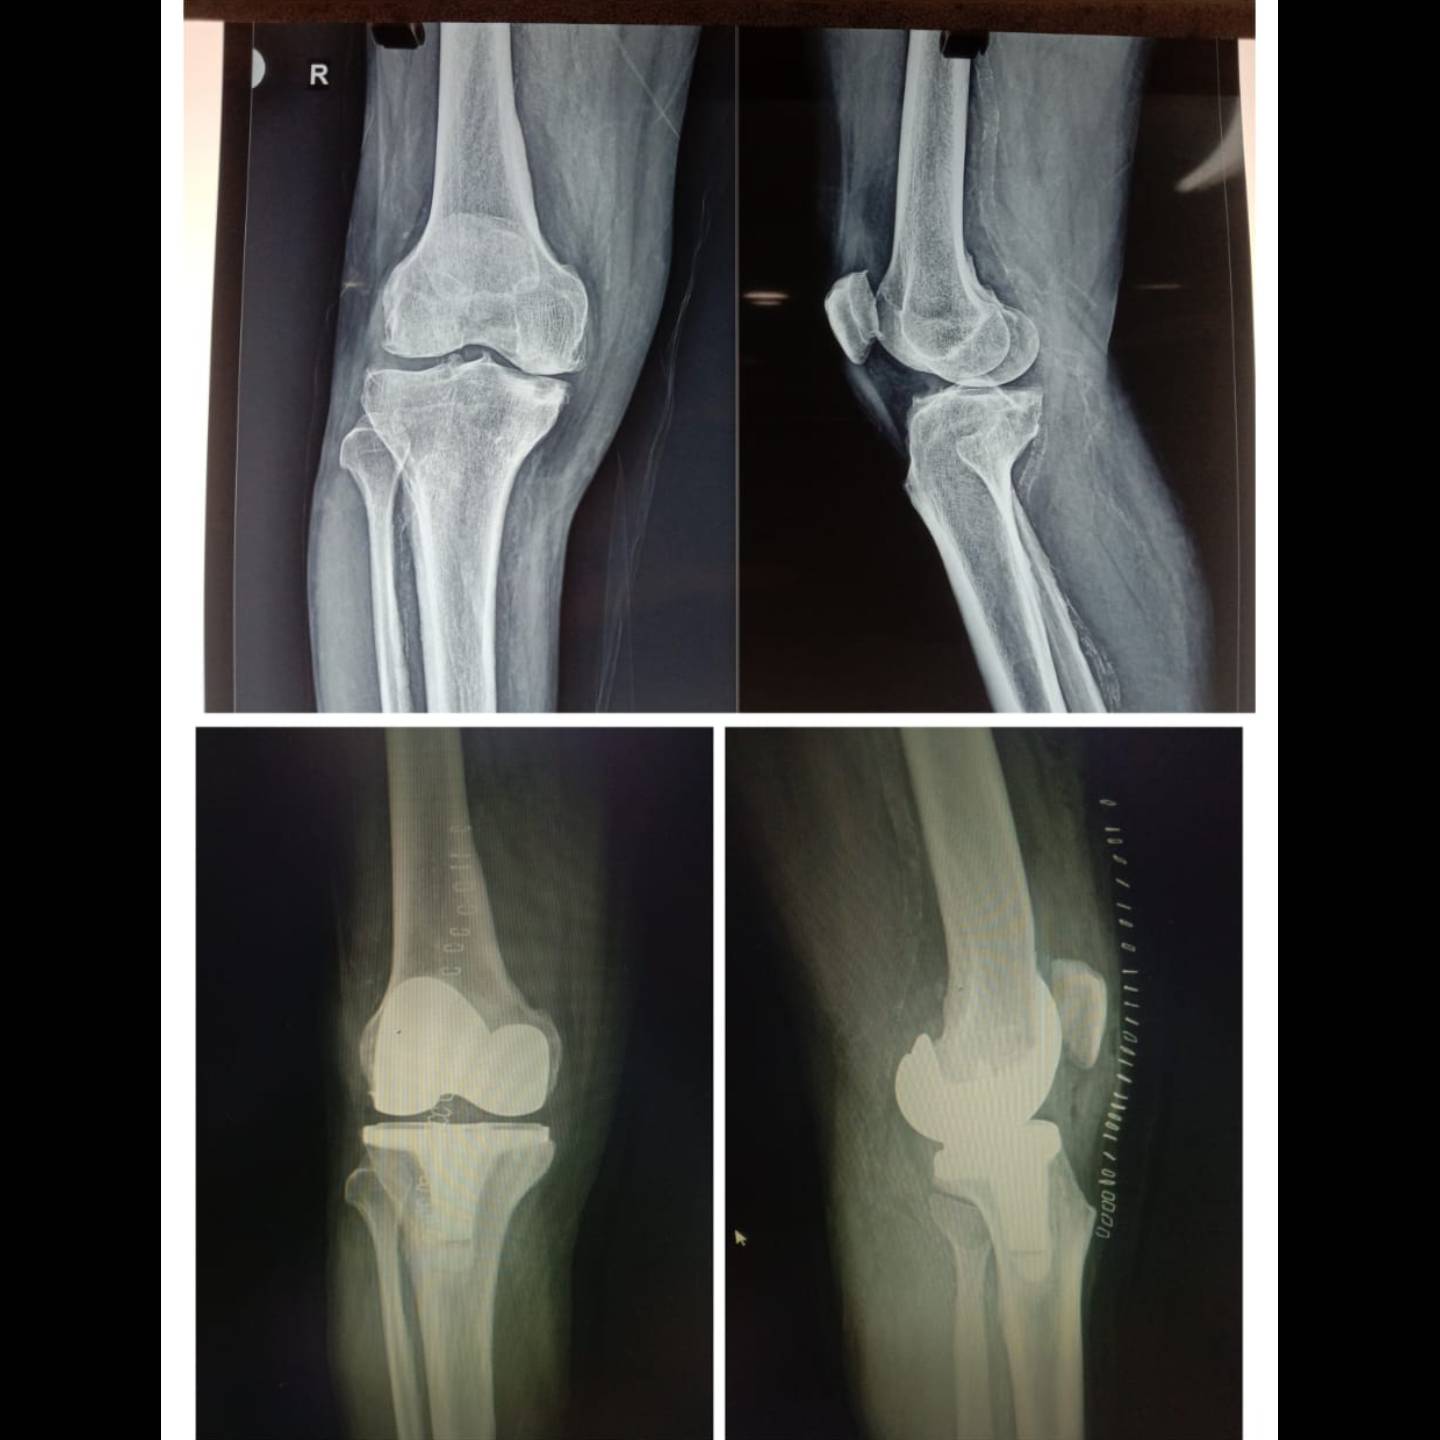

66 y gentleman with severely painful arthritic knee...total knee replacement.